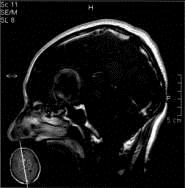

问题 病历摘要:??患者男性,56岁,因右侧视力下降伴视野缺损2个月来院就诊,诉头痛,无明显头晕,无视物重影,无恶心呕吐,无肢体抽搐,无肢体乏力,胃纳佳,大小便正常,既往史无特殊,入院检查:神志清楚,言语清楚,体毛分布正常,左侧视力4.6,右侧视力4.0,粗侧右颞侧视野缺损,左侧正常,颈软,四肢肌张力正常,肌力正常,病理征(-)。 在巨型动脉瘤手术中,若术中需要夹闭载瘤动脉,下述那些方法可先预测夹闭后的效果可能是好的?提示:本例病患采用开颅手术治疗

答案 ACEF